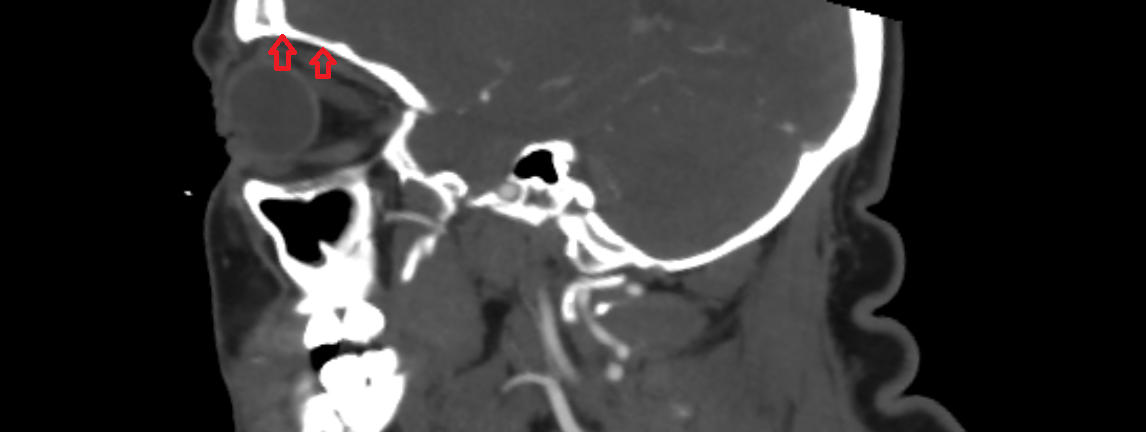

- Temporomandibular joint